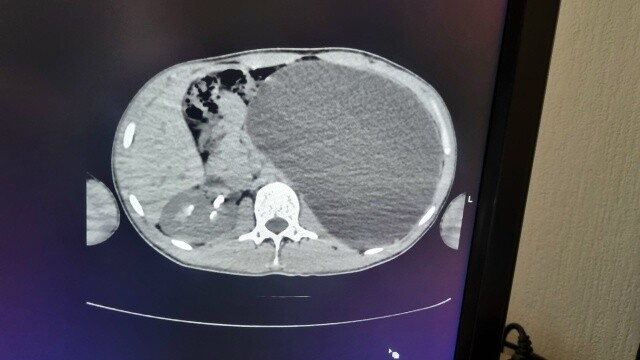

«Это была случайная находка. Парень к нам поступил из амбулаторного звена. Он устраивался на работу. Ему перед трудоустройством сделали УЗИ, нашли объемное образование в брюшной полости. Мы стали обследовать, оказалось, что это гидронефроз левой почки с отсутствием паренхимы (основная ткань органа, выполняющая его функции – Прим. ред.)», – отметила детский хирург-уролог Ирина Живолуп.

Гидронефроз – это заболевание почки, которое характеризуется стойким нарастающим расширением ее полостей, атрофией почечной паренхимы в результате нарушения циркуляции крови и оттока мочи из почки. Эта патология приводит к повышению внутрилоханочного давления и повреждению почечной ткани. Часто гидронефроз длительное время протекает бессимптомно и обнаруживается случайно при ультразвуковом обследовании.

«У нашего пациента почка достигла размеров пятилитровой бутылки! Она занимала почти весь объем живота и давила на все соседние органы. Это была настоящая бомба замедленного действия: любая травма, случайный удар в живот – и мешок мог разорваться внутри», – рассказали в ДГКБ № 1.